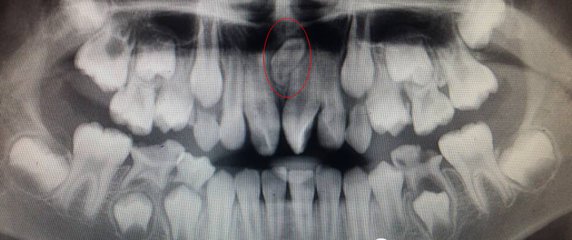

兒(er) 童牙齒齲壞嚴(yan) 重,一般需要在拍片檢查後才能確定是否能夠保留牙齒,如果可以治療後保留的牙齒一般醫生是不會(hui) 輕易進行拔除的。因為(wei) 嚴(yan) 重齲壞的牙齒,可以查看是否傷(shang) 害到牙髓組織了,如果沒有,可以進行試補牙,沒有異常就可以正式補牙充填,如果有異常疼痛或者是已經露出牙髓的情況,也可以做根管治療來保留牙齒。

一般不要輕易拔牙,但是如果出現了多生牙的情況要不要拔除呢?深圳愛康健口腔醫院兒(er) 牙醫生表示,多生牙,就是多出來的牙齒,所以在檢查確認後,一般是需要拔除,如果不拔除,就會(hui) 導致牙齒畸形,影響咀嚼功能和美觀。